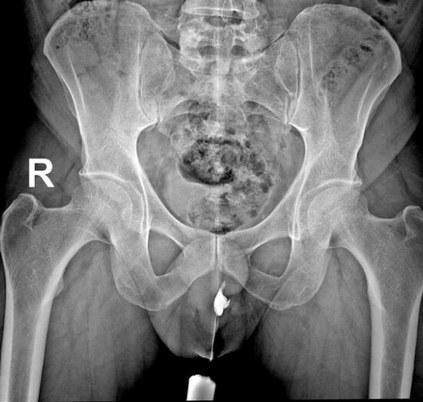

In this study, we aim to initiate the development of Radiology Foundation Model, termed as RadFM.We consider the construction of foundational models from the perspectives of data, model design, and evaluation thoroughly. Our contribution can be concluded as follows: (i), we construct a large-scale Medical Multi-modal Dataset, MedMD, consisting of 16M 2D and 3D medical scans. To the best of our knowledge, this is the first multi-modal dataset containing 3D medical scans. (ii), We propose an architecture that enables visually conditioned generative pre-training, allowing for the integration of text input interleaved with 2D or 3D medical scans to generate response for diverse radiologic tasks. The model was initially pre-trained on MedMD and subsequently domain-specific fine-tuned on RadMD, a radiologic cleaned version of MedMD, containing 3M radiologic visual-language pairs. (iii), we propose a new evaluation benchmark that comprises five tasks, aiming to comprehensively assess the capability of foundation models in handling practical clinical problems. Our experimental results confirm that RadFM significantly outperforms existing multi-modal foundation models. The codes, data, and model checkpoint will all be made publicly available to promote further research and development in the field.